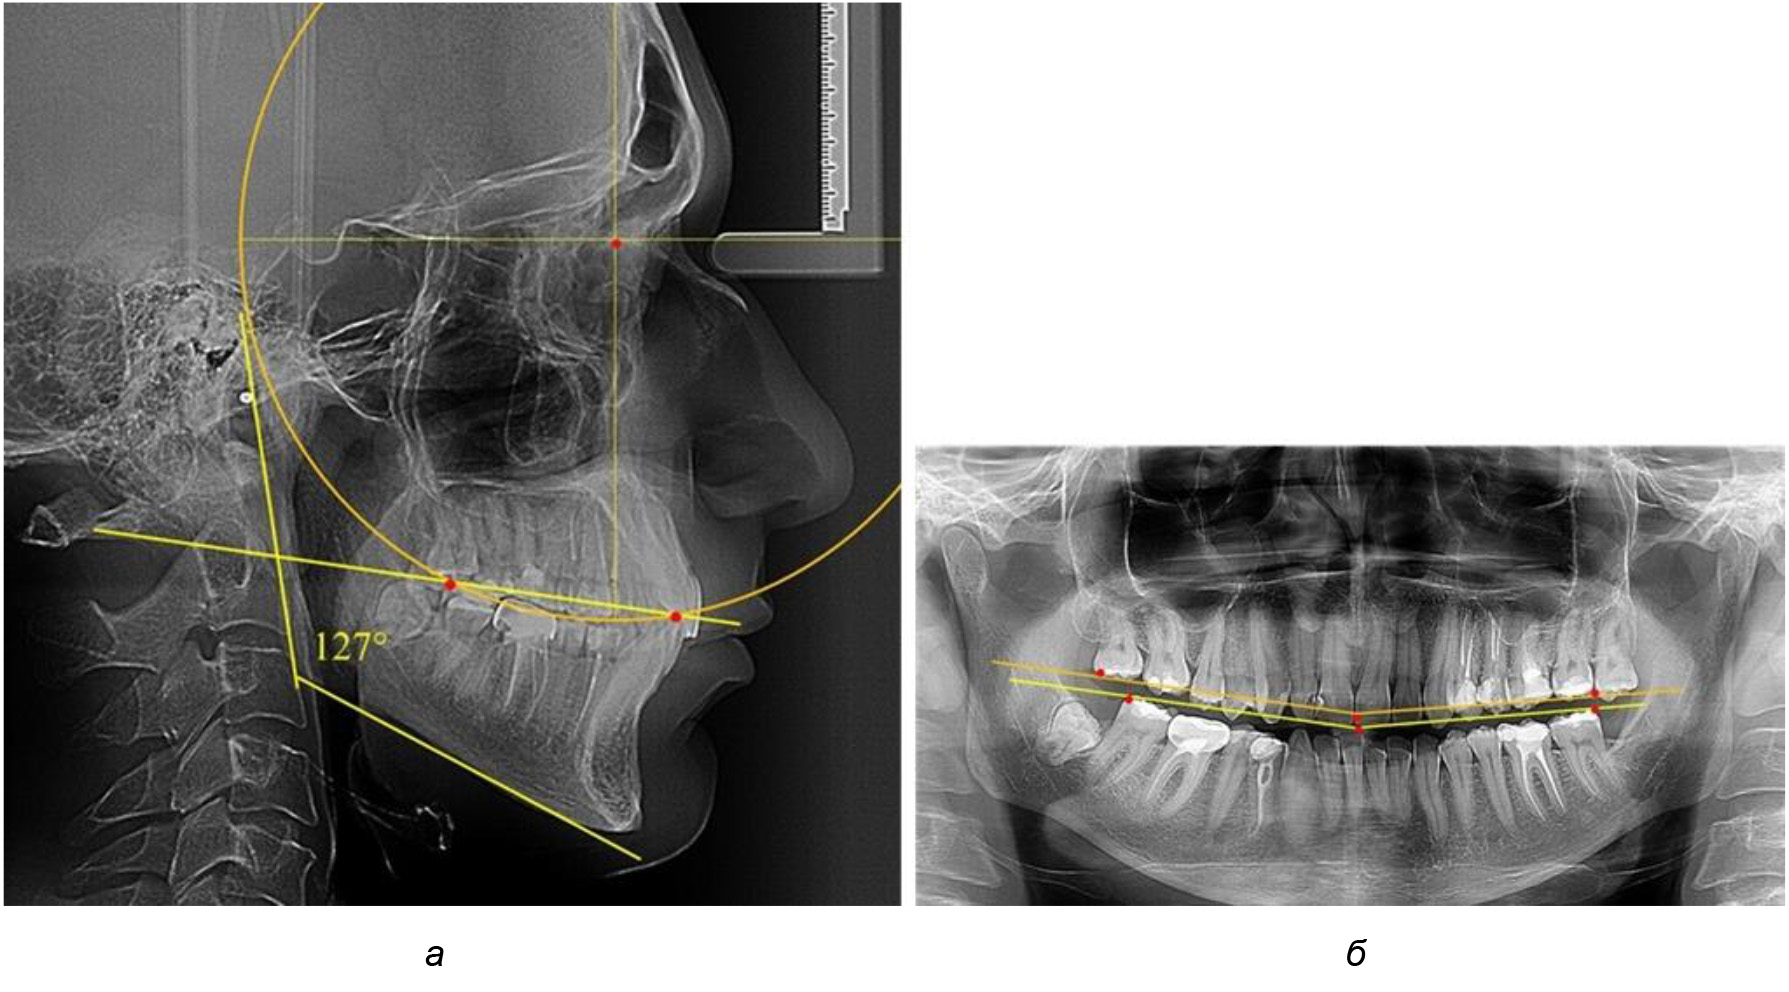

В 3-ю подгруппу вошли ТРГ и ОПТГ 14 человек 1-й группы, что составило (22,58 ± 5,31) % от общего количества людей 1-й группы. Величина угла нижней челюсти в среднем составила (114,85 ± 2,87)° и характеризовала горизонтальный тип нижней челюсти.

Глубина кривой Spee в среднем по 2-й подгруппе составил (2,94 ± 0,47) мм, что было меньше, чем в других подгруппах. Деление величины радиуса круга к длине окклюзионной линии составило 1,616 ± 0,02 (рис. 4).

Рис. 4. Особенности кривой Spee на ТРГ (а) и ОПТГ (б) у людей с горизонтальным типом лица